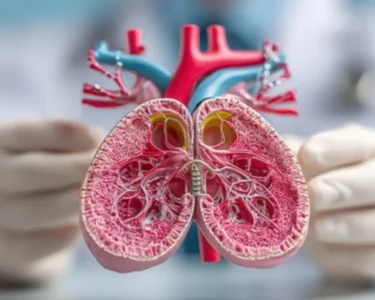

“The cold weather increases the viscosity of the blood, making it thicker and harder to flow, especially in individuals with pre-existing cardiovascular conditions,” explained Dr. Ajay Kumar, a neurologist at Raj Hospital. “This, coupled with the body’s natural response to conserve heat by constricting blood vessels, creates a dangerous situation.”

The patients affected range in age, but a disproportionate number are elderly individuals and those with underlying health issues such as hypertension, diabetes, and high cholesterol. Symptoms reported include sudden weakness or numbness in the face, arm, or leg, difficulty speaking, severe headache, and vision problems. Early detection and treatment are crucial in minimizing the long-term effects of a stroke.